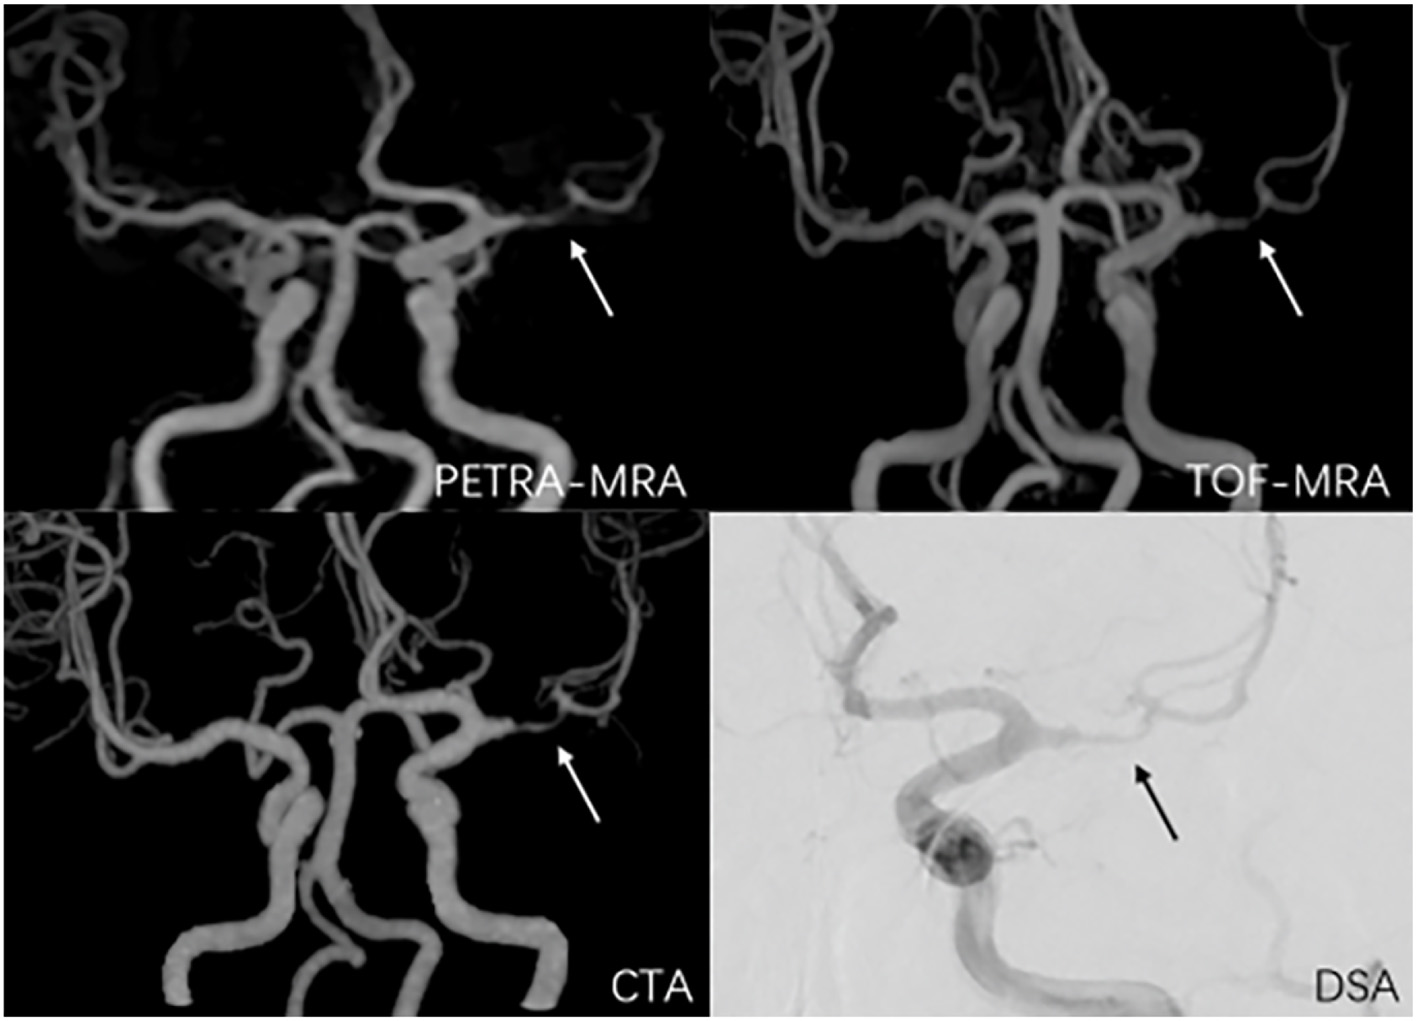

The degree of stenosis acquired with TOF-MRA and CTA was greater than that with DSA (63.0% ± 15.8% vs. 54.0% ± 18.6%, P < 0.01; 61.0% ± 18.6% vs. 54.0% ± 18.6%, P < 0.01, respectively). However, no marked difference in the degree of stenosis quantification was observed between PETRA-MRA and DSA (55.3% ± 17.7% vs. 54.0% ± 18.6%, P = 0.13). No obvious difference in lesion length was noted between PETRA-MRA and DSA (P = 0.06), between TOF-MRA and DSA (P = 0.17), and between CTA and DSA (P = 0.78). The examples from two patients were shown in Figures 4, 5.

Figure 4. A 38-year-old man with symptomatic left middle artery stenosis. The arrow marks the location of the lesion. The degree of stenosis was 80.9% on PETRA-MRA, 89.1% on TOF-MRA, 88.3% on CTA, and 82.3% on DSA. Lesion length was 6.98 mm on PETRA-MRA, 7.41 mm on TOF-MRA, 7.83 mm on CTA, and 6.5 4 mm on DSA.